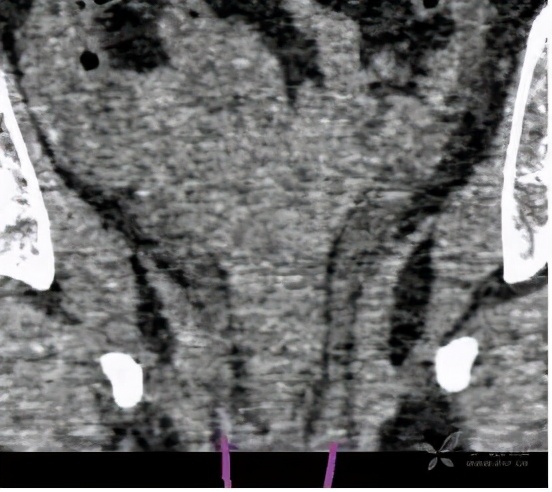

在增强CT检查的时候,得到了如下检查图像

检查图像显示,该病人的双侧输尿管于膀胱开口处过低,还伴有左侧部分双肾盂、输尿管畸形,这些图像给我们的印象是:是不是存在异位开口的可能?

输尿管异位开口是指输尿管开口不在膀胱三角区两侧的先天性畸形。

双肾双输尿管并输尿管口异位80%以上见于女性,多伴有重复肾输尿管畸形。